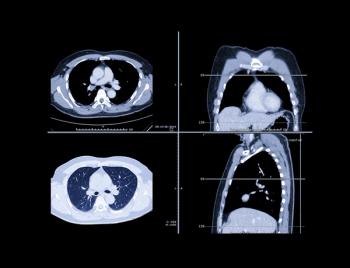

Although early computed tomography (CT) screening was associated with improved cure rate for patients with lung cancer, less than 6% of the population that is eligible receives it.